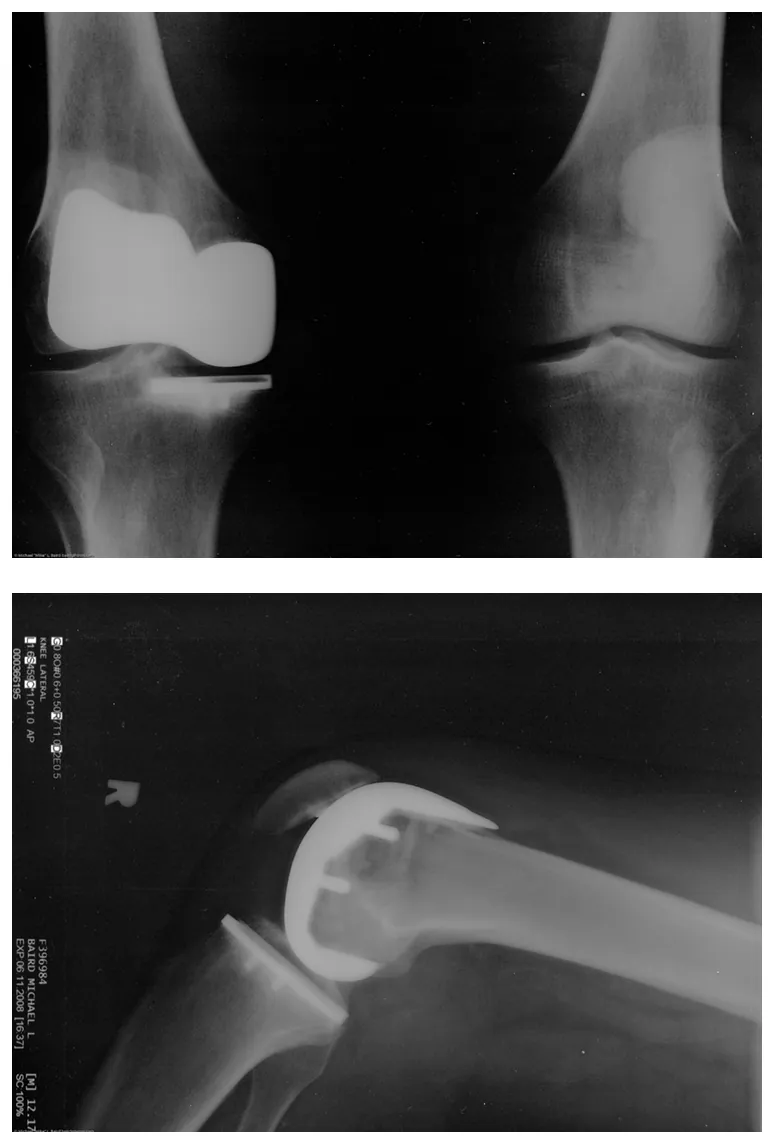

Many people have experienced the slipperiness of walking on ice. However, many parts of the body, especially the joints, have much smaller coefficients of friction—often three or four times less than ice. A joint is formed by the ends of two bones, which are connected by thick tissues. The knee joint is formed by the lower leg bone (the tibia) and the thighbone (the femur). The hip is a ball (at the end of the femur) and socket (part of the pelvis) joint. The ends of the bones in the joint are covered by cartilage, which provides a smooth, almost glassy surface. The joints also produce a fluid (synovial fluid) that reduces friction and wear. A damaged or arthritic joint can be replaced by an artificial joint (Figure 5.3). These replacements can be made of metals (stainless steel or titanium) or plastic (polyethylene), also with very small coefficients of friction.

Two X-x rays of an artificial knee replacement are shown.

Figure 5.3 Artificial knee replacement is a procedure that has been performed for more than 20 years. In this figure, we see the post-op x rays of the right knee joint replacement. (credit: Mike Baird, Flickr)